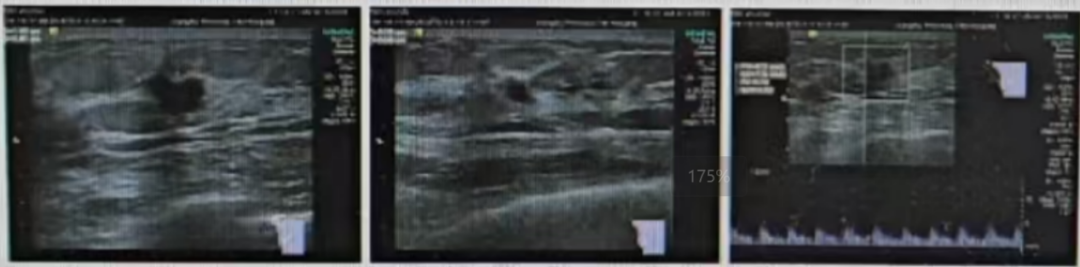

·乳腺核磁共振(MRI)

1、双侧乳腺呈多量型(ACR-c型);

2、右乳上方结节影,考虑为乳腺癌,BIRADS 6类,右乳外上结节及小片状强化灶,BIRADS 4a类,DCIS待排除;

3、双侧乳腺增生,BIRADS 2类。

图3乳腺MRI结果